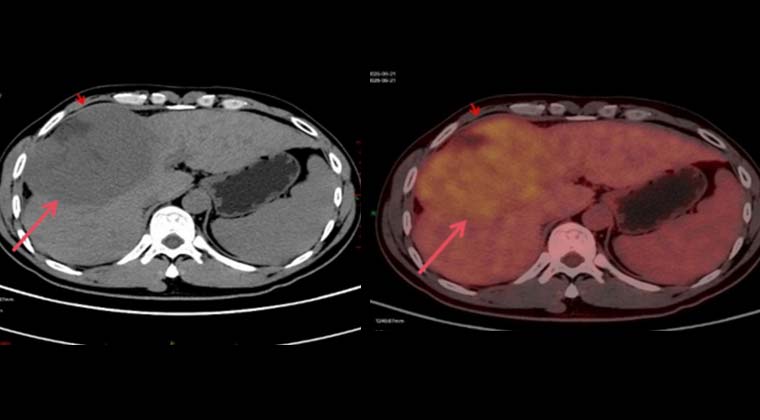

Пациент: мужчина, 41 год

Гепатоцеллюлярная карцинома, стадия BCLC C / CNLC IIIa

Симптом: боль в животе

Диагноз: 09-21 PET-CT выявило крупное образование в правой доле печени

(Изображения до лечения)